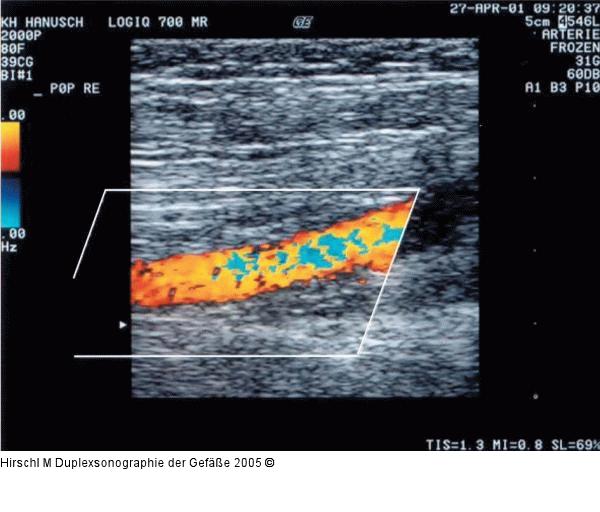

Abbildung 8: Duplexsonographie - PRF Zu niedrig gewählte PRF im Bereich einer nicht stenosierten A. poplitea. In der Gefäßmitte Umschlag von hellgelb zu hellblau während der systolischen Strömungsphase. |

Zu niedrig gewählte PRF im Bereich einer nicht stenosierten A. poplitea. In der Gefäßmitte Umschlag von hellgelb zu hellblau während der systolischen Strömungsphase. |